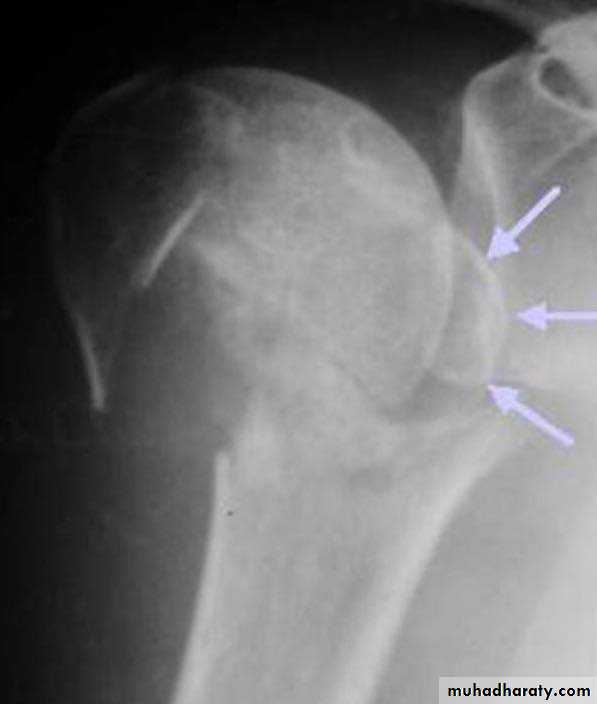

X RAY

27

28

Three part fracture

Its account for 5%of proximal

Humeral fracture

Fracture line involve 3_4 part

Two part are displaced more than

1cm

Or more than 45 degrees